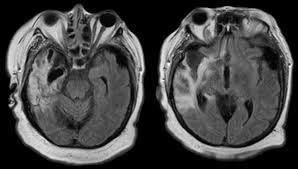

Hsv Encephalitis Mri Radiopaedia - Herpes Encephalitis Ct Scan Ct Scan Machine - It is a common finding on brain mri and a wide range of differentials should be considered 1.. Two subtypes are recognized which differ in demographics, virus, and pattern of involvement. 10 public playlist includes this case The changes spare the basal ganglia, a feature which is helpful in distinguishing an mca infarct with hemorrhagic transformation from herpes simplex encephalitis. Radiopaedia is free thanks to our supporters and advertisers. The changes spare the basal ganglia, a feature which is helpful in distinguishing an mca infarct with hemorrhagic transformation from herpes simplex encephalitis, the diagnosis in this case.

It is usually bilateral but asymmetrical. Hsv encephalitis | radiology case | radiopaedia.org. Note the high signal in the caudate heads and putamen on flair. Hypertrophic pachymeningitis is a condition where there is localized inflammatory thickening of the dura. For a general discussion, and for links to other system specific manifestations, please refer to the article on coccidioidomycosis. Radiopaedia is free thanks to our supporters and advertisers. Reference osborn a, et al. The changes spare the basal ganglia, a feature which is helpful in distinguishing an mca infarct with hemorrhagic transformation from herpes simplex encephalitis, the diagnosis in this case.

Two subtypes are recognized which differ in demographics, virus, and pattern of involvement. Become a gold supporter and see no ads. Bilateral temporal lobe t2 hyperintensity refers to hyperintense signal involving the temporal lobes on t2 weighted and flair imaging. Hypertrophic pachymeningitis is a condition where there is localized inflammatory thickening of the dura. Limbic encephalitis, mca ischaemia, tumours, effects of seizures) hyperintense t2 signal in the medial temporal lobes, inferior frontal lobes and insula basal ganglia are usually spared Reference osborn a, et al. Given the history of fever and seizures coupled with the mri findings of bilateral mesial temporal lobe changes, herpes encephalitis requires clinical consideration. The changes spare the basal ganglia, a feature which is helpful in distinguishing an mca infarct with hemorrhagic transformation from herpes simplex encephalitis, the diagnosis in this case. Mri demonstrates extensive edema in the right temporal lobe with areas of intrinsic high t1 signal, in keeping with hemorrhage. It is estimated to occur in ~2% of pati. The differential diagnoses include limbic encephalitis (paraneoplastic), gliomatosis cerebri, and status epilepticus. It is reasonable to obtain an mri when patients are asymptomatic to ensure that no other abnormality is present which may be causing a recurrent chemical meningitis (e.g. Axial t2 prominent swelling, increase t2 signal involving the left temporal lobe and insular cortex.

Axial t2 prominent swelling, increase t2 signal involving the left temporal lobe and insular cortex. Two subtypes are recognised which differ in demographics, virus, and pattern of involvement. Multilocularis.the larval stage is the cause of hydatid disease in humans 1. Cerebral malaria is a rare intracranial complication of a malarial infection. The changes spare the basal ganglia, a feature which is helpful in distinguishing an mca infarct with hemorrhagic transformation from herpes simplex encephalitis, the diagnosis in this case.